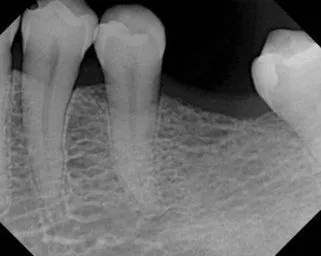

Root Canal Treatment

Before

After